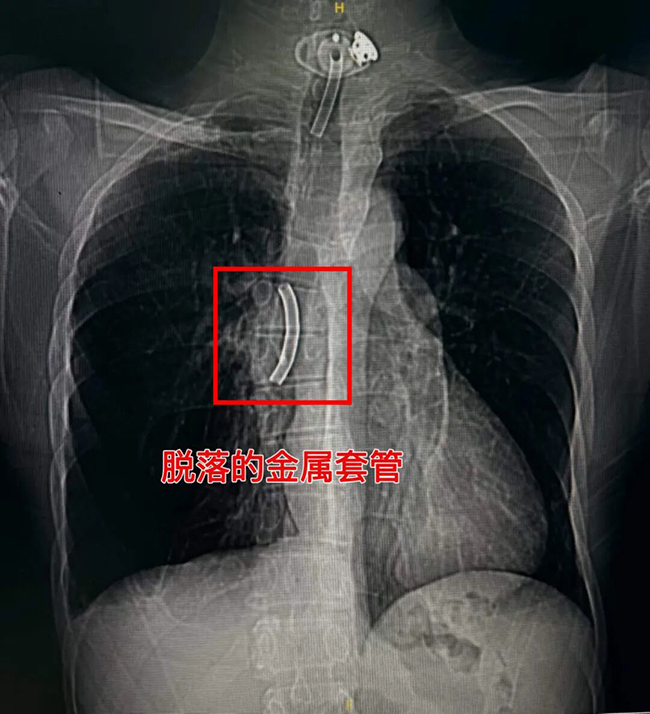

意外发生在前不久的一个深夜。李先生留置在气管内的金属套管突然发生断裂落入到气道深部,当地医院无法取出,在做完简单处理后他被紧急转至我院急诊。CT检查显示:断裂的金属套管已移位至右主支气管。异物位置深、形态不规则,再加上李先生特殊的气道结构,取出难度极大。